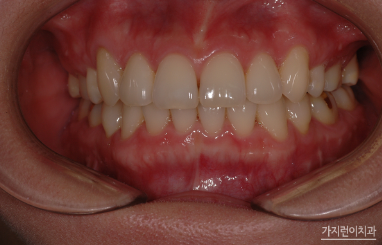

무조건 발치를 진행하지 않아도 되는데요. 치아 사이의 법랑질을 약간 삭제해 공간을 얻는 치간삭제 방법이나, 전악후방 이동이나, 악궁확장 등의 방법으로도 공간을 확장해볼 수 있습니다. 물론 비발치교정이 불가능한 경우도 있기 때문에 각도나 위치에 따라 발치가 필요한 경우도 있는데요. 그런 경우에는 고집 피우지 않고 설계한 플랜대로 발치를 진행해 공간을 충분히 두고 교정을 해두는 게 좋습니다.

덧니 치아교정은 심각도에 따라 교정시기를 차별화해야 하는데요. 벗어난 정도가 심하지 않다면 시작 시기가 중요하지 않지만 심한 경우에는 초등학교때 시작하는 게 좋습니다. 최근에는 교정 술기의 진화로 인해 다양한 교정장치를 만나볼 수 있게 되었는데요. 금속, 세라믹, 플라스틱 등 다양하지만 각 장치별로 기능 차이가 있기 때문에 교정과 담당원장님과 상의 후 결정해보는 게 좋겠습니다.

한마디로 덧니교정은 성장기에 진행해도 좋지만 성인이 된 이후에도 받아볼 수 있는데요. 덧니로 인해 불편함이나 구강질환이 걱정된다면 바로 치아교정을 시작하는 게 좋겠습니다. 덧니 교정이라고 해서 부분교정으로만 극복할 수 있는 것은 아닌데요. 덧니 형태와 전체적인 치열 상태를 확인한 후 구강 구조와 골격 등을 살펴 플랜을 수립해야 하겠습니다.